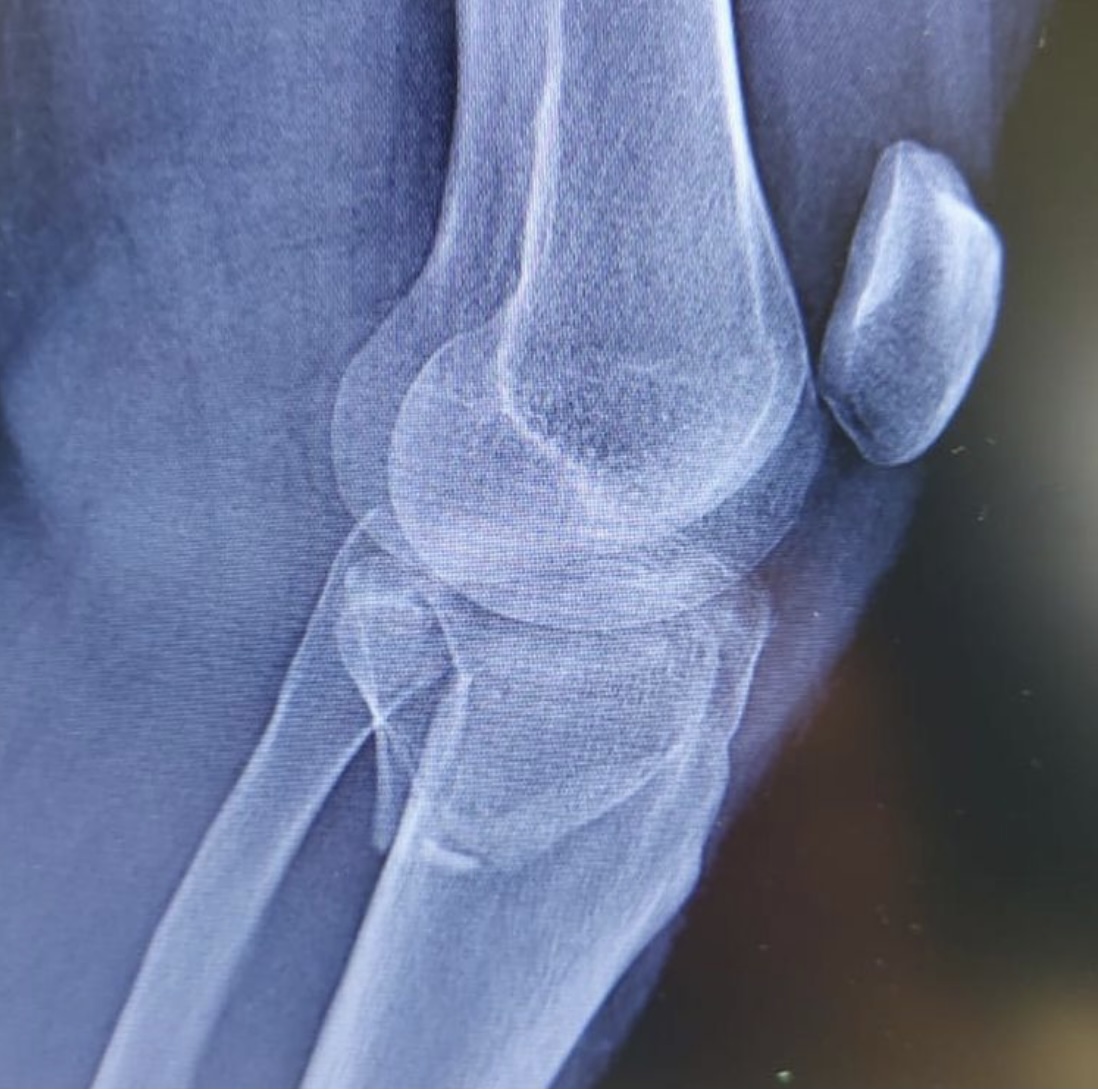

На операционном столе пациент с травмой в результате падения с самоката — многооскольчатый перелом верхнего суставного конца большеберцовой кости с разрывом боковых связок.

«Выполнен остеосинтез пластинами и винтами, восстановлены связки коленного сустава, — рассказывает хирург — травматолог ГКБ 7 Казани Руслан Ильгизарович Закиров. — Самокат в последнее время стал достаточно популярным средством попадания в травматологическое отделение нашей клиники. Большая скорость, маленькие колёса и неровности на дороге, необходимость объезжать пешеходов на тротуаре…. все это пополняет печальную статистику дорожно — транспортных происшествий».